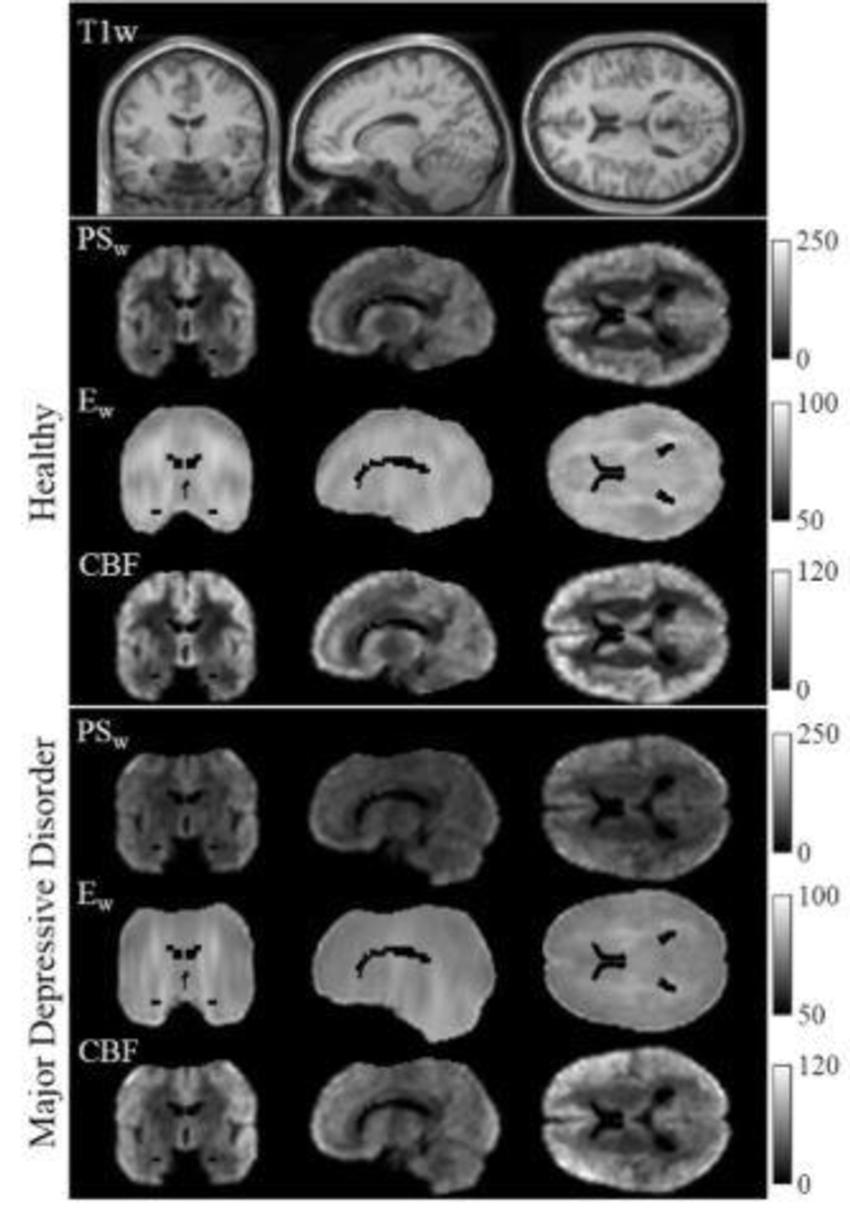

Dr. Wengler and colleagues at the Renaissance School of Medicine at Stony Brook University in Stony Brook, N.Y., recently studied connections between MDD and disruptions in the blood-brain barrier (BBB), a network of blood vessels and tissue that protects the brain from foreign substances. Using a new MRI technique they developed called intrinsic diffusivity encoding of arterial labeled spins (IDEALS), they looked at BBB water permeability, or the movement of water out of the blood vessels and into the brain tissue.

Comparison of results in 14 healthy individuals and 14 MDD patients found that less water moved from inside the blood vessels to outside in the MDD patients, representing disrupted BBB integrity. This difference was particularly large in two regions of the brain: the amygdala and the hippocampus.

Figure 1 (Wengler). Healthy brain vs. brain with major depressive disorder.